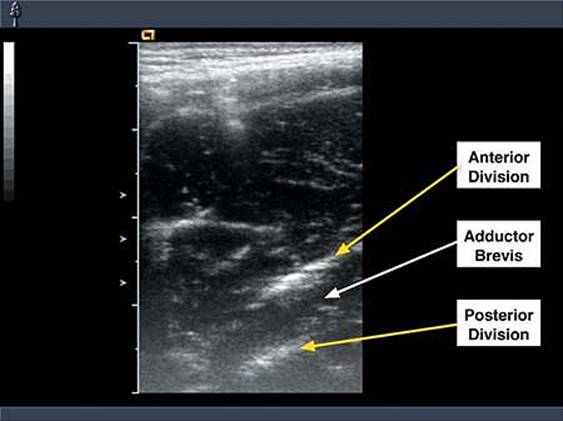

Ultrasound Landmarks: The lateral adductor brevis muscle. The anterior division of the obturator nerve usually lies superficial to the adductor brevis muscle. The posterior division of the nerve usually lies deep to the adductor brevis muscle. Both divisions produce broad, flat, hyperechoic images at the lateral border of the adductor brevis muscle. The obturator artery, which is sandwiched between the obturator internus and externus muscles.

Figure 38-2. Sonogram of the obturator nerve divisions in the medial thigh. The anterior and posterior divisions are seen in short axis view (transverse cross section) separated by the adductor brevis muscle. Large tick marks are 10 mm apart.